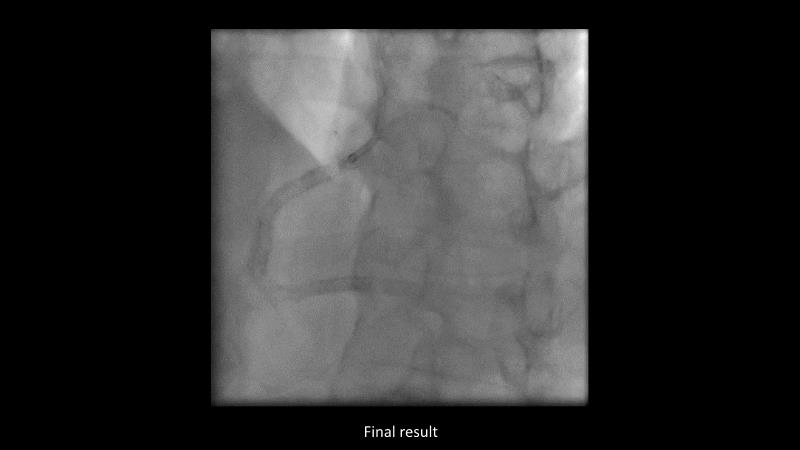

Maximize patient clinical outcomes in complex percutaneous coronary interventions (PCIs) by joining this session. Discover how accurate patient evaluation, advanced imaging/functional modalities, optimized procedures, and the Cre8 EVO device contribute to improved safety and efficacy, and review the challenges associated with DES implantation in complex PCIs.